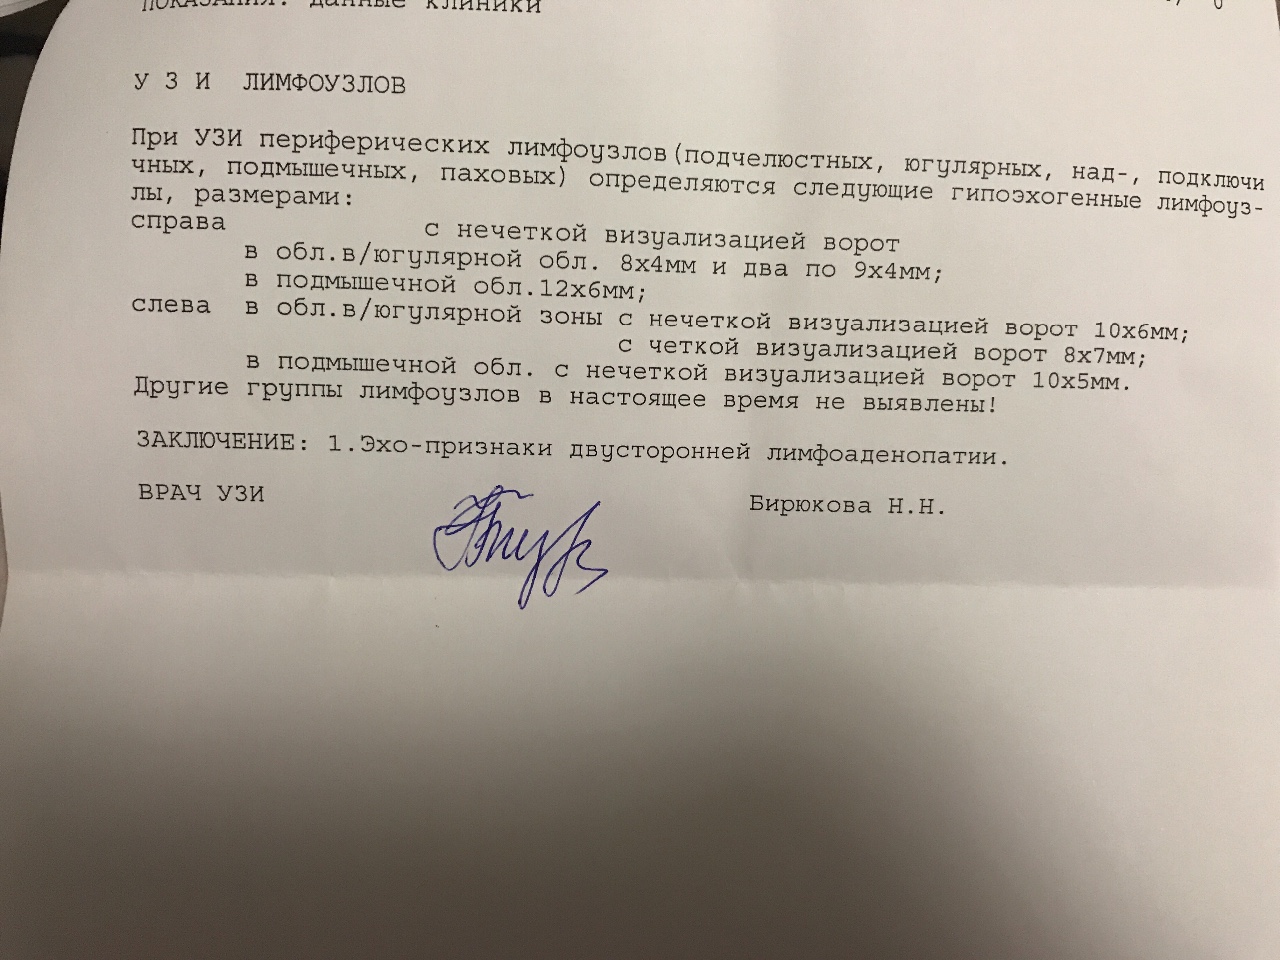

УЗИ лимфоузлов при лимфоме Ходжкина